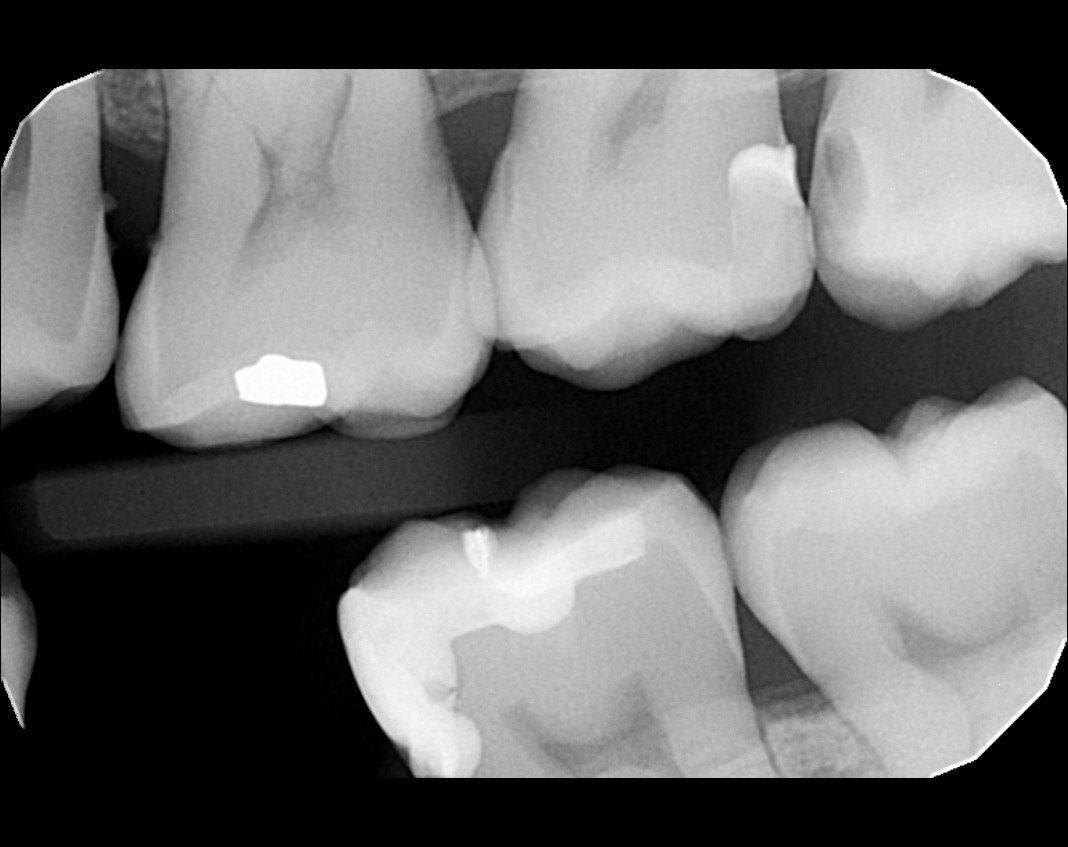

ACJ Quiz - Restorative Dentistry X-Ray 01

Question 1: What materials cannot be seen in the print of the X ray?

Question2: Which surface shows overhang?

Question 3: Which option is not evident on the print of the X ray?

Question 4: Which options cannot be seen in the print of the X ray?